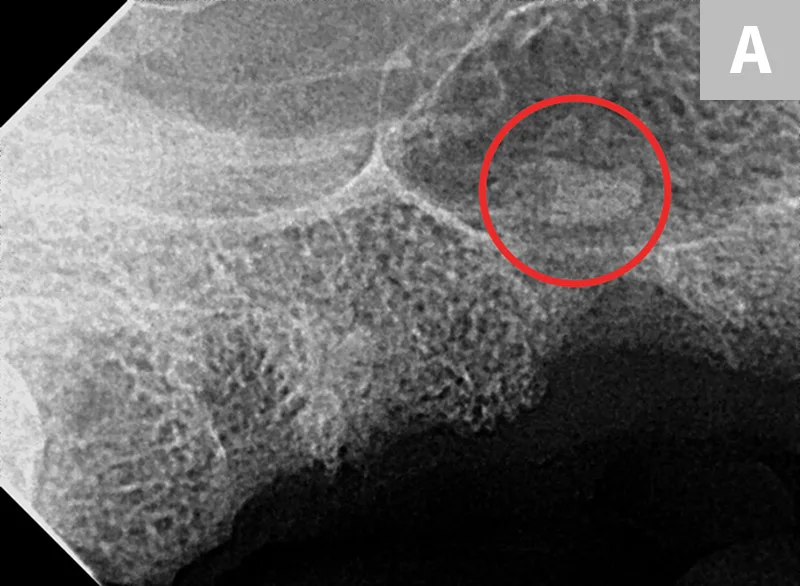

selected slide image

FIGURE 6

1 / 3

Iatrogenic fracture of the left rostral mandible after extraction of the left mandibular canine tooth (A; arrows). Same patient with iatrogenic jaw fracture after extraction (B); significant bone loss from periodontal disease was present, which contributed to this complication. Dilacerated root of the left mandibular first molar in a small-breed dog (C). The first molar in these breeds is often very large as compared with the width of the mandible. The hook on the mesial root can make extraction more challenging.